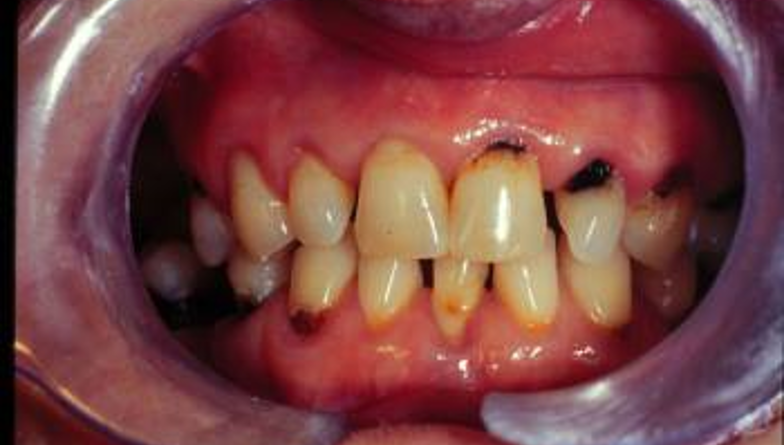

La enfermedad periodontal – Salud dental con la Dr. Bernarda Alcántara

La enfermedad periodontal es una patología de alta incidencia y tiene un impacto significativo en enfermedades crónicas no transmisibles, como la Diabetes Mellitus. La Dra. Bernarda nos brinda información sobre los síntomas y los tratamientos disponibles.